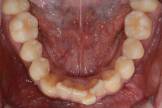

부분교정 (아래 앞니)

아래 앞니가 삐뚤삐뚤한 것을 교정하러 오신 환자분입니다. 6개월간 세라믹 교정장치를 사용하여 치료하였습니다.